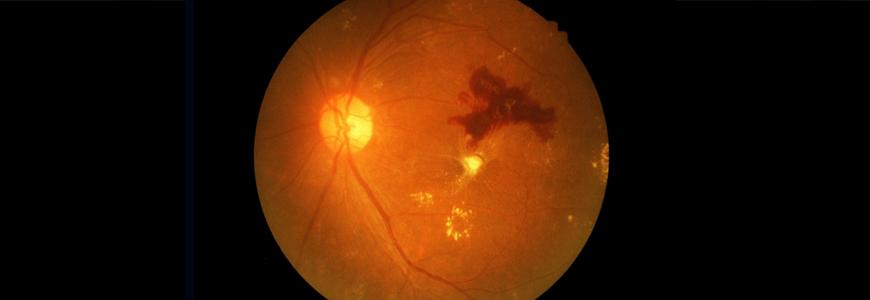

A New Model for Diabetic Retinopathy Screening and Triage

Using a nonmydriatic imaging device to screen patients for diabetic retinopathy (DR) in primary care clinics, Duke researchers found that a remote diagnosis model is as effective a tool as a tradit